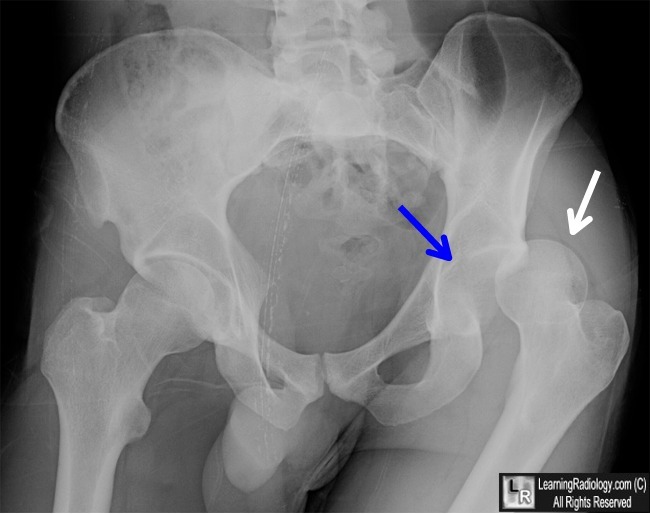

21. Segond 골절이란 무엇이며, 임상적으로 암시하는 바는 무엇인가?

Segond 골절은 외측인대 부착부의 근위 외측 경골의 견열 골절을 말한다. 골절 파편은 매우 작을 수 있다. 방사선 사진 상으로 보기에 매우 힘듦에도 불구하고, 흔하게 전방십자인대 파열과 반월상 연골판 손상이 동반된다.

△ D는 Segond 골절에 해당. 근위 외측 경골의 견열 골절(화살표)에 해당한다.